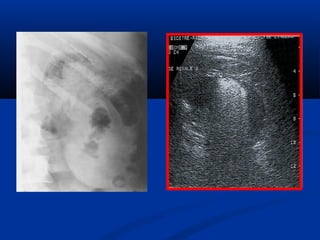

Lao thaänLao thaän

Sieâu aâm:Sieâu aâm:

• **Thaän vaø nieäu quaûn:Thaän vaø nieäu quaûn:

• - Voâi hoaù trong thaän- Voâi hoaù trong thaän

• - Chít heïp = giaõn heä beå- Chít heïp = giaõn heä beå

ñaøiñaøi

• - Hình aûnh coäng: taïo- Hình aûnh coäng: taïo

hang, xoang tuûy…hang, xoang tuûy…

• - Thaän teo nhoû, voâi- Thaän teo nhoû, voâi

hoaùhoaù

• ** Baøng quang :Baøng quang : daøydaøy

vaùchvaùch

Öu theá UIV trong lao nieäuÖu theá UIV trong lao nieäu

SA giuùp ích höôùng daãnSA giuùp ích höôùng daãn